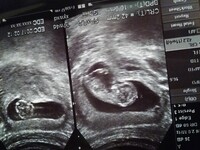

妊娠12週目 胎児の大きさ・体重・エコー写真、流産の可能性はかなり低く 妊娠12週(12w)の胎児のエコー写真・超音波写真 妊娠12週目 妊娠4カ月 受精から70~76日目 胎児の大きさ 頭殿長(座高)が6cm 体重は10g~15gほど 妊娠12週(12w)になると今まで急成長を続けてきた赤ちゃんも、このあたりでペースダウン。 妊娠11週 ママの悩みQ&A 妊娠中はおなかの赤ちゃんの成長、体重管理や体の悩みについて、育児中は赤ちゃんの発育、予防接種や健診、母乳・ミルク・離乳食、お世話や遊びなどなど、いろんな疑問や不安を抱えています。 そんな妊娠中から育児中のママたちのお悩みに、産婦人科や小児科の医師、助産師、保育士など各分野の専門家がていねいにお答えします 不安で毎日生きている気がしません。 今、初めての妊娠11週目です。 お腹の中の赤ちゃんがちゃんと生きているか分からなくて心配で毎日不安です。 周りに、予兆や前触れもなく12週目で心肺停止していた、などの話をよく聞きます。 不安な度に産婦人科に行くのもお金がかかって破産してしまいます。 そこで、友達に聞いたのですが、 不安なら妊娠検査薬やれ

妊娠11週、胎児の様子は? 妊娠11週ころになると、赤ちゃんの体のパーツもだいぶできてきます。 目にはまぶた、耳には耳たぶ、口には唇、鼻も高くなって鼻の穴もできます。 下あごや頬も発達してきます。 超音波検査(エコー)で見ると、ずいぶん人間らしい顔つきになっています。 また、性別を区別する外性器は、妊娠11週の終わりごろにはできてきます 妊娠12週、症状なく不安です。 現在12週になりました。 10週の時に検診に行って以来(心拍確認出来てます)1ヶ月に1回の検診なので、次の検診まで後2週間あります。 春にも一度妊娠しましたが、赤ちゃんが確認出来ず8週で稽流流産の手術をしています。 今の症状は胸の張り、たまに、げっぷ悪阻がありますが、ピーク時は1日3回位吐いていたのも落ちつきました 妊娠3ヶ月(8週・9週・10週・11週) プレママタウンの一部の記事をユニ・チャームのムーニーサイトへ移行いたしました。 あらかじめご了承ください。 28件 妊娠3ヶ月の赤ちゃんは「胎芽(たいが)」からようやく「胎児」と呼ばれる姿へ成長します。